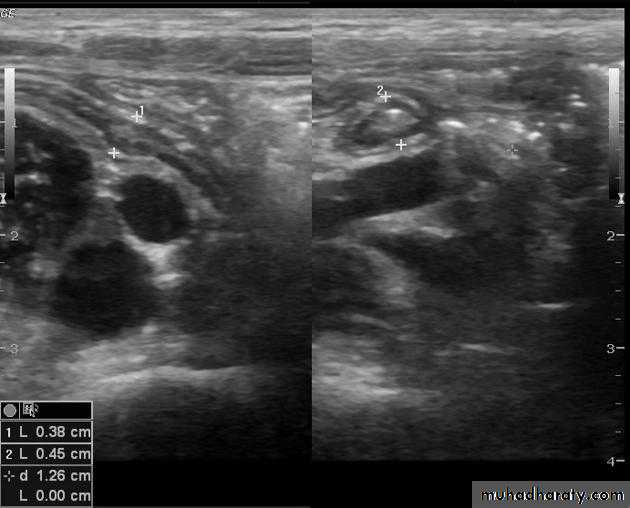

Signs of acute appendicitis on US:

• Thickened edematous appendix [diameter > 6 mm].

• Non-compressible blind ending tubular structure.• Appendicolith.

• Local free peritoneal fluid.

• Sentinel dilated bowel loop.

• Complication: abscess, inflammatory mass.

Limitations of US:

• The normal appendix is often not visualized• Retrocecal appendicitis may be obscured.

• The negative predictive value of a negative US examination is not as high as for CT.